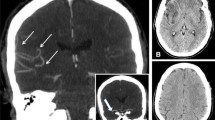

In healthy controls, PJ34 has been shown to recruit the arteriolar cerebral vasodilation reserve more strongly in neonatal mice than in adult mice, thereby playing a beneficial role during stroke [53]. Collateral BF may be established either during arterial occlusion or after reperfusion, depending on the age of the animal, and with the recruitment of one or both routes, depending on the experimental procedure. In 7-day-old rat pups, the collateral blood supply tends to be established very rapidly, immediately after the end of the ischemia procedure (50 min) when compared to most of adult rat models, in which the collateral blood supply is effective 2 to 3 h after the beginning of the procedure (Fig. 6). Aging may lead to the rarefaction of cerebral collaterals, leading to collateral recruitment failure with significantly impaired pial collateral dynamics (smaller diameter, decrease in red blood cell velocity), thereby aggravating ischemic injury by reducing penumbral blood flow [54]. Together, these data suggest that the collateral blood supply is stronger and established more rapidly in neonatal pups than in adults [8].

Collateral blood supply following focal ischemia in neonatal and adult rats. A Anatomy of the circle of Willis. B Permanent MCA occlusion (pMCAo) and transient CCA occlusion (tCCAo) are required to create an infarct in rat pups. C pMCAo is sufficient to create an infarct in adult rats. D, E One hour after focal ischemia, the increase in mean blood flow velocities in the contralateral ICA and BT provides evidence of the early establishment of the collateral blood supply through the circle of Willis and the cortical anastomoses in rat pups. No increase was observed in the adult rats at this time point. Data provided for neonatal stroke from references [9, 16, 32, 33], and for adult stroke from [55]